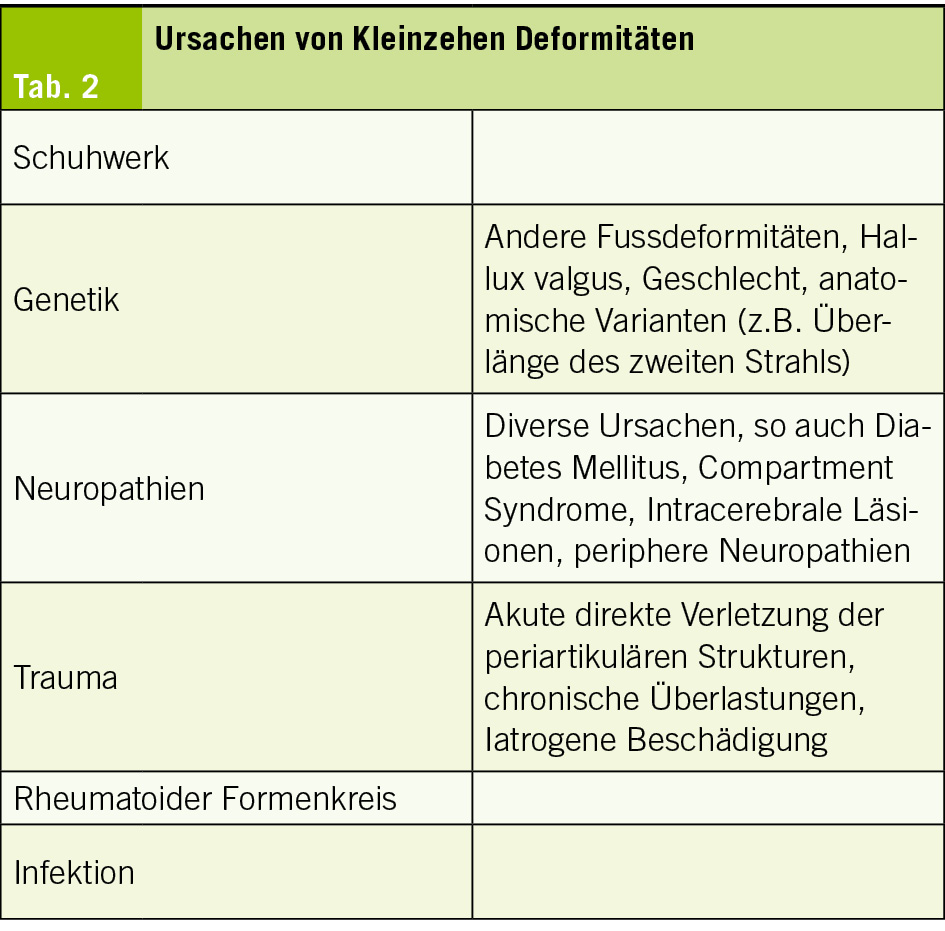

Gründe für die Entwicklung von Kleinzehendeformitäten können Instabilitäten der periartikulären Strukturen sein, vor allem der plantaren Platte, Instabilitäten des Fusses oder des MTP Gelenks, Rheumatologische Erkrankungen mit entsprechender Degeneration, akute oder chronische Traumatisierung im Rahmen einer Überlastung (32, 33, 35). Weitere sind in der Tab. 2 aufgelistet.